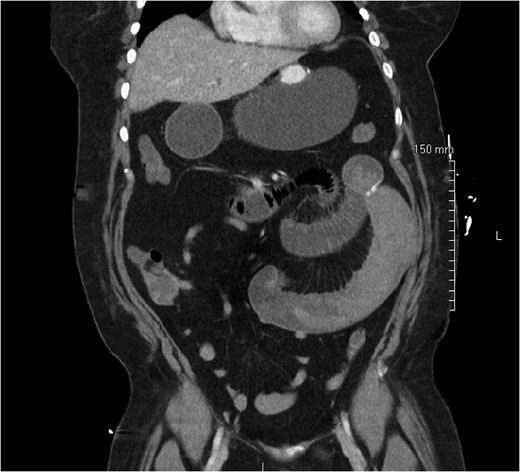

On post-operative day 1, she complained of nausea, vomiting and abdominal pain, though symptoms were consistent with an expected post-operative course. On post-operative day 2, however, she developed a leukocytosis of 15 600/mm3 and an intermittent tachycardia ranging from 85 to 118 bpm. An abdominal CT was obtained, which demonstrated a SBO with a transition point distal to the jejunojejunostomy anastomosis (Fig. 1). The patient was taken to the operating room for diagnostic laparoscopy. Upon initial inspection, there was no evidence of a mechanical cause for obstruction such as kinking or adhesions. However, the bowel proximal to the common channel appeared dilated and discolored (Fig. 2). Esophagogastroduodenoscopy (EGD) was performed to inspect the luminal mucosa, which was pink and well-perfused. Inspection distal to the jejunojejunostomy revealed a 50 cm section of bowel that was firm and appeared to be the point of obstruction. An enterotomy was made in the proximal common channel, which revealed a large intraluminal clot (Fig. 3). This was removed piecewise with a combination of suction and manual extraction (Fig. 4). There was no evidence of active bleeding or leakage from the jejunojejunostomy anastomosis. Due to the friability of the intestinal walls and absence of active bleeding, the anastomosis was not revised and the enterotomy was primarily closed.

Abdominal CT demonstrating SBO with a transition point distal to the jejunojejunal anastomosis.

Abdominal computed tomography (CT) is an important adjunct used to diagnose SBO and can also rule out other post-operative complications such as fluid collection from anastomotic leak, abscess or extraluminal hemorrhage. While post-operative tachycardia, leukocytosis and abdominal pain are reasons for emergent diagnostic laparoscopy after bariatric procedures, in our patient CT was utilized first due to the intermittent nature of the tachycardia and the resolution of symptoms with pain medication.